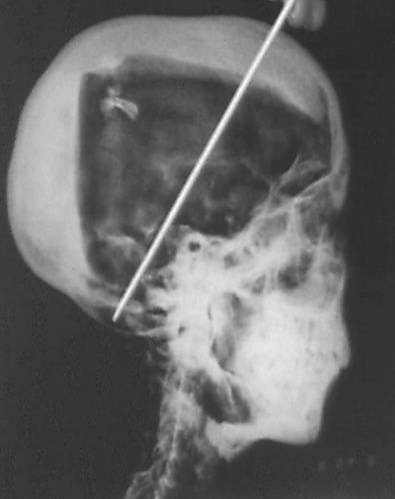

В 1968 году Р. Г. Харрисон, профессор анатомии, использовал портативный рентгеновский аппарат для повторного исследования мумии Тутанхамона. Харрисон быстро обнаружил, что Картер расчленил мумию, о чём не упоминается в его публикации, но видно на фотографиях разворачивания. Состояние мумии, обложенной ватой и зафиксированной современными бинтами, ухудшилось с тех пор, как её в последний раз фотографировала команда Картера в 1926 году[47][27].

Рентгеновские снимки выявили два уровня смолы внутри черепа. Один из них появился, когда тело лежало на спине, и скопился на затылке; другой, когда голова была откинута сильно назад, оседал в верхней части черепа. В полости черепа также находились небольшие костные фрагменты, которые, как первоначально полагал Харрисон, были результатом процесса бальзамирования. Тот факт, что были обнаружены фрагменты черепа, заставил многих предположить, что царь был убит ударом по голове, но рентгеновский снимок не смог ни подтвердить, ни опровергнуть эту теорию. Его возраст на момент смерти снова был оценён примерно в 18 лет, а предполагаемый рост при жизни — 168,9 см[47]. Серологический анализ, проведённый той же командой, показал, что у Тутанхамона и мумии KV55 была одна и та же группа крови, что свидетельствовало о возможном родстве[50].

15 января 2005 года под руководством Захи Хавасса мумия Тутанхамона была извлечена из гробницы и подвергнута компьютерной томографии с помощью портативного аппарата. Сканирование позволило провести точную судебно-медицинскую реконструкцию его тела и лица, а также получить дополнительные свидетельства причины его смерти. Результаты показали, что костные фрагменты внутри черепа сместились, что указывает на то, что травматическое повреждение головы произошло уже после смерти, и убийство в результате удара тупым предметом было исключено[51].